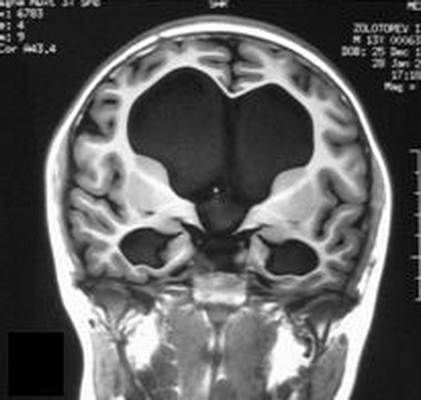

![Водянка головного мозга на МРТ]()

Водянка головного мозга при МР-сканировании в коронарной проекции